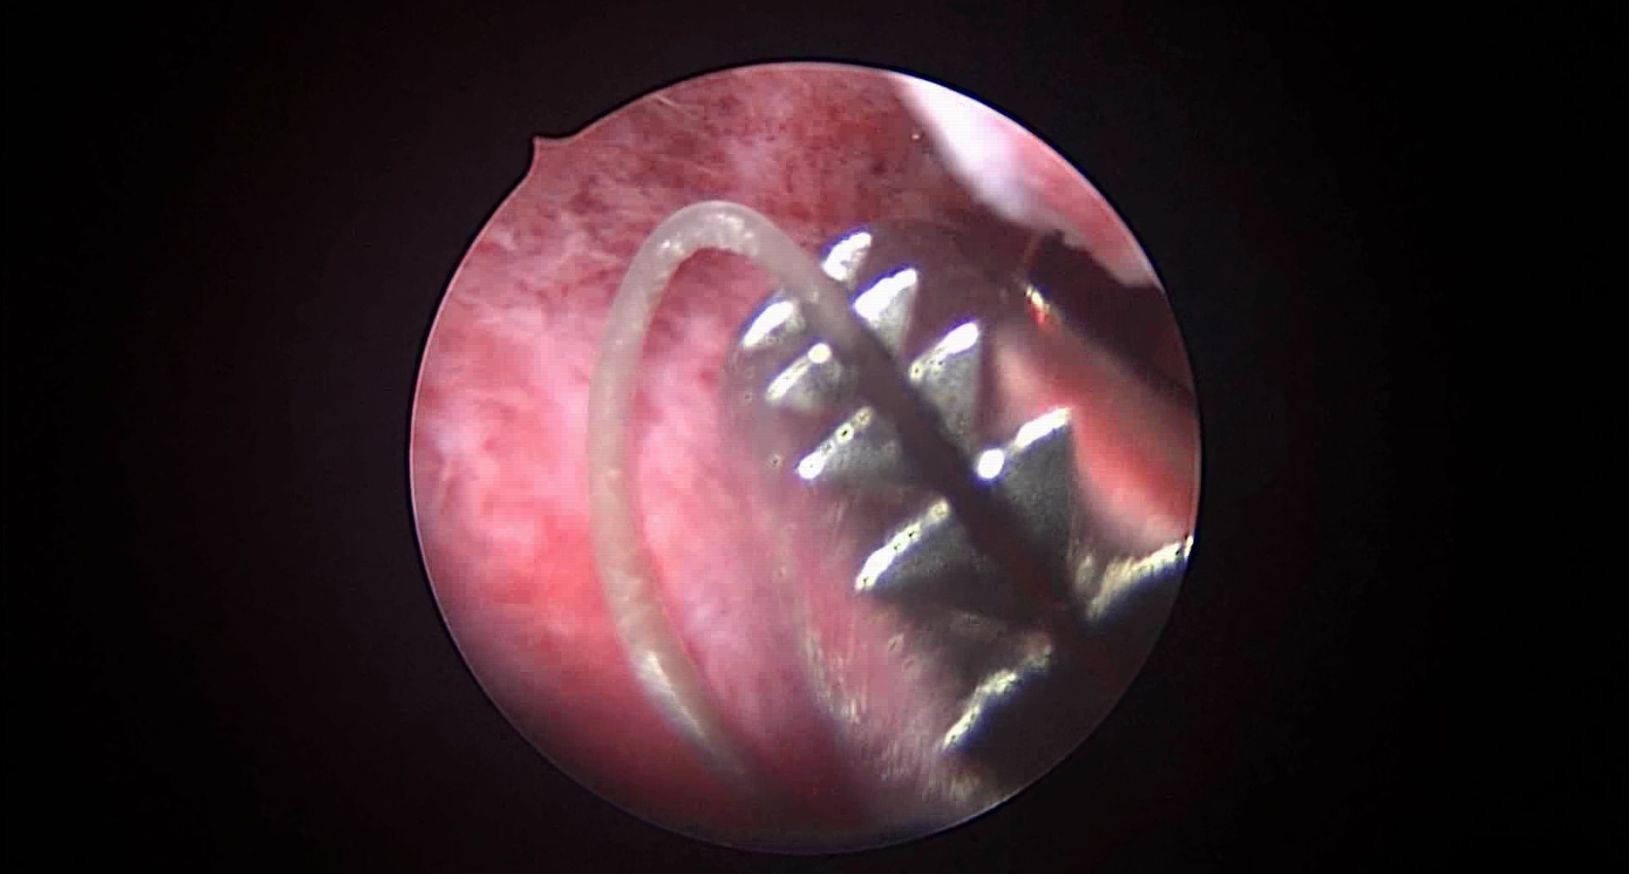

患者41岁,G4P2,顺产2次。因异常子宫出血于2023年12月在外院行宫腔镜检查,取内膜病检为增生晚期及分泌早期宫内膜组织,另见宫内膜息肉,术后药物治疗效果不佳,月经周期不规律。本次阴道不规则流血10+天,量多就诊。宫腔镜下尝试线结扣宫底锚定曼月乐,将结推人宫底肌层很困难,最后采用不锈钢挂钩固定。用曼月乐尾丝连接环与不锈钢挂钩,将挂钩插入宫底肌层,异物钳原位固定曼月乐,退出宫腔镜,结束手术。术后患者未回院复查节育环位置。